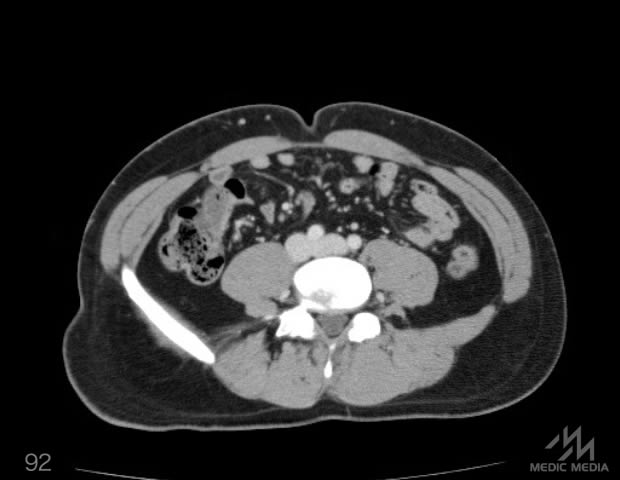

造影CT

消化器

肝区域